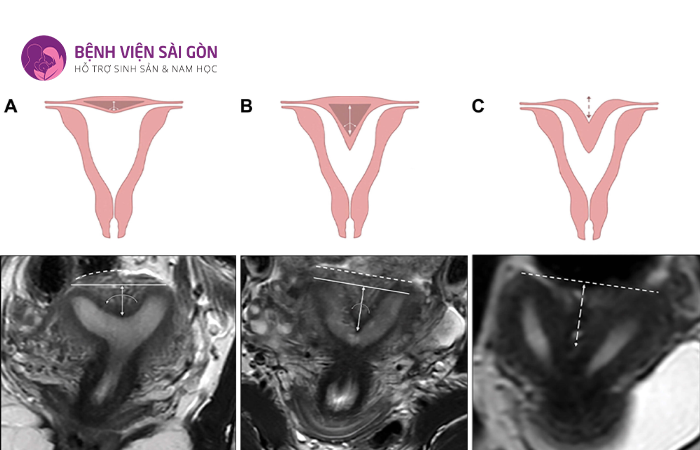

3.2 Tử cung có vách ngăn

Loại tử cung dị dạng này thường gặp nhất có chiếm khoảng 40%. Người bị dị dạng loại này có thể được phát hiện nhờ phương pháp chụp X-quang, siêu âm hoặc khi tiến hành nội soi ổ bụng.

Hai tử cung có thể liên quan đến vách ngăn không hoàn chỉnh hoặc hoàn chỉnh. Tình trạng này gây cản trở quá trình mang thai, nguyên nhân dẫn đến sảy thai hoặc thai nhi chậm phát triển.

Chính vì thế, bác sĩ sẽ tiến hành mổ tử cung trở về bình thường nếu phát hiện tử cung có vách ngăn.